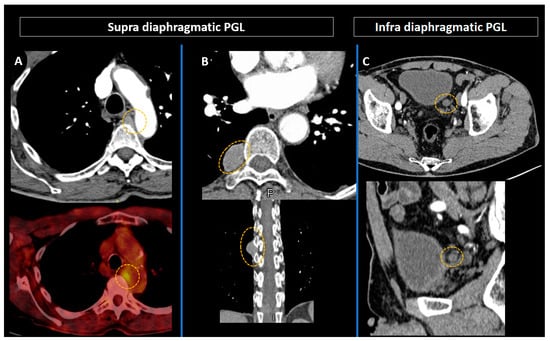

3.5. Head and Neck Parangangliomas: Specific Concerns

3.6. Specific Concern: How to Manage Asymptomatic SDHx Mutation Carriers?